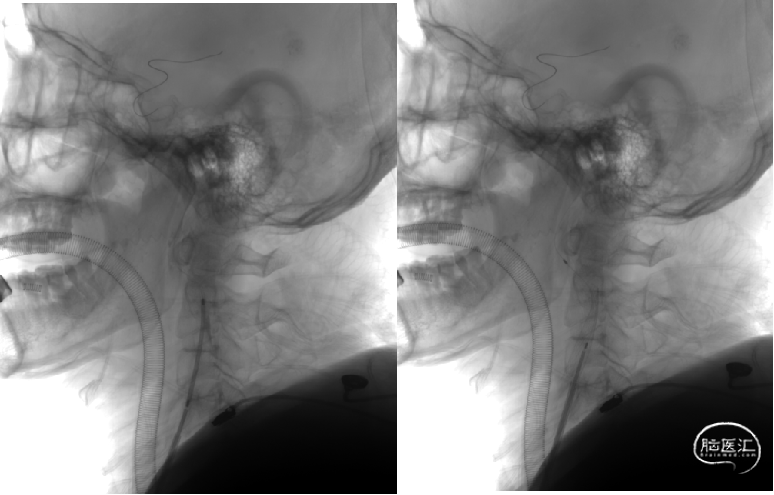

球囊泄除后即刻造影提示血管扩张良好,局部出现夹层。

Neuroform EZ4.5*20 支架顺利置入病变处,稳定释放。

支架释放后造影提示血流改善明显。